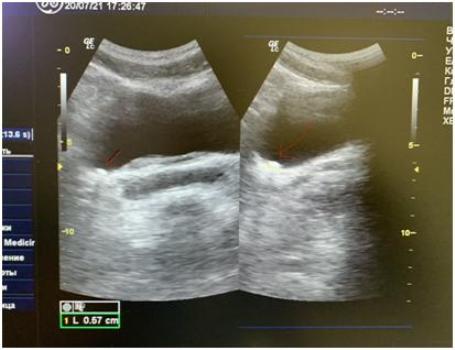

По УЗИ - конкремент размером 6 мм визуализируется в н\3 правого мочеточника.

Через 2 дня лечения: по УЗИ - конкремент определяется в устье правого мочеточника.

После пятой процедуры акустической стимуляции на аппарате Интрафон-3 по УЗИ - конкремент лоцируется в полости мочевого пузыря, пиелоэктазия справа отсутствует, пациент отмечает исчезновение болей в правом боку.